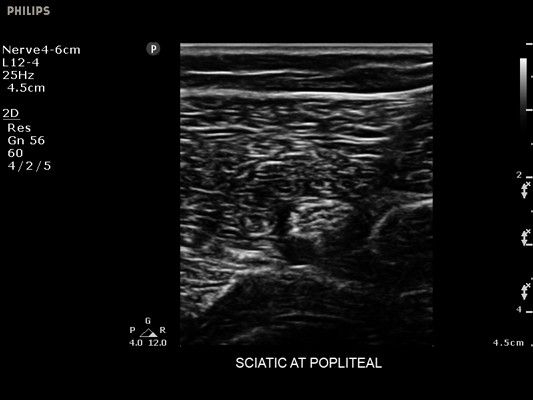

• Метки центральной линии на датчиках L12-4 и C6-2 для упрощения внеплоскостной навигации

• Диагностика нервов

• Линейный УЗИ датчик Philips L12-4